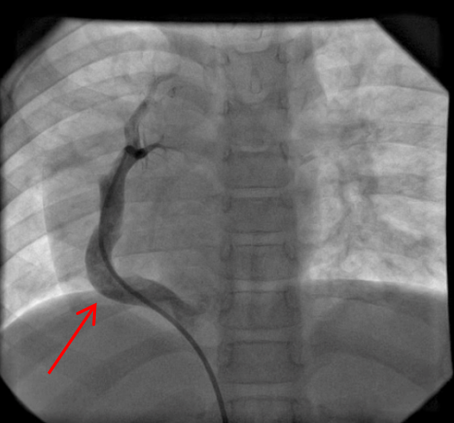

Routine laboratory analysis, including a complete blood count and metabolic panel, is normal. A postero-anterior chest roentgenogram is shown in Figure 1. Chest computed tomography (CT) without IV contrast (Figure 2), and gadolinium enhanced magnetic resonance angiogram (Figures 3 and 4) are also obtained. A decision is made to perform a cardiac catheterization (Figures 5 and 6) for further evaluation.

Figure 3

The red arrow (Figures 7, 8, 9, and 11) shows a large scimitar vein. Chest CT (Figure 8) shows partial anomalous pulmonary venous return from the right lower pulmonary vein into the inferior vena cava (IVC) and right-sided pulmonary hypoplasia with consequent dextro-position of the heart into the right hemithorax. The gadolinium-enhanced angiography cardiac magnetic resonance imaging (MRI) (Figure 9) with three-dimensional reconstruction (Figure 10, Video 1) confirms the diagnosis, which shows aortopulmonary collaterals from the descending abdominal aorta to the right lower lung lobe (one dot), large anomalous pulmonary vein, the scimitar vein (two dots), draining the right lower lung to the IVC (three dots). The right heart is within normal limits for size.

A cardiac catheterization is performed. Right pulmonary artery and descending aorta injections (Figures 11 and 12) show a large scimitar vein and aortopulmonary collaterals to the right lung (orange arrow, Video 2). Coil occlusion of the aortopulmonary collateral is done at the time of the cardiac catheterization. Qp:Qs was 1.3:1 on both MRI and on cardiac catheterization.